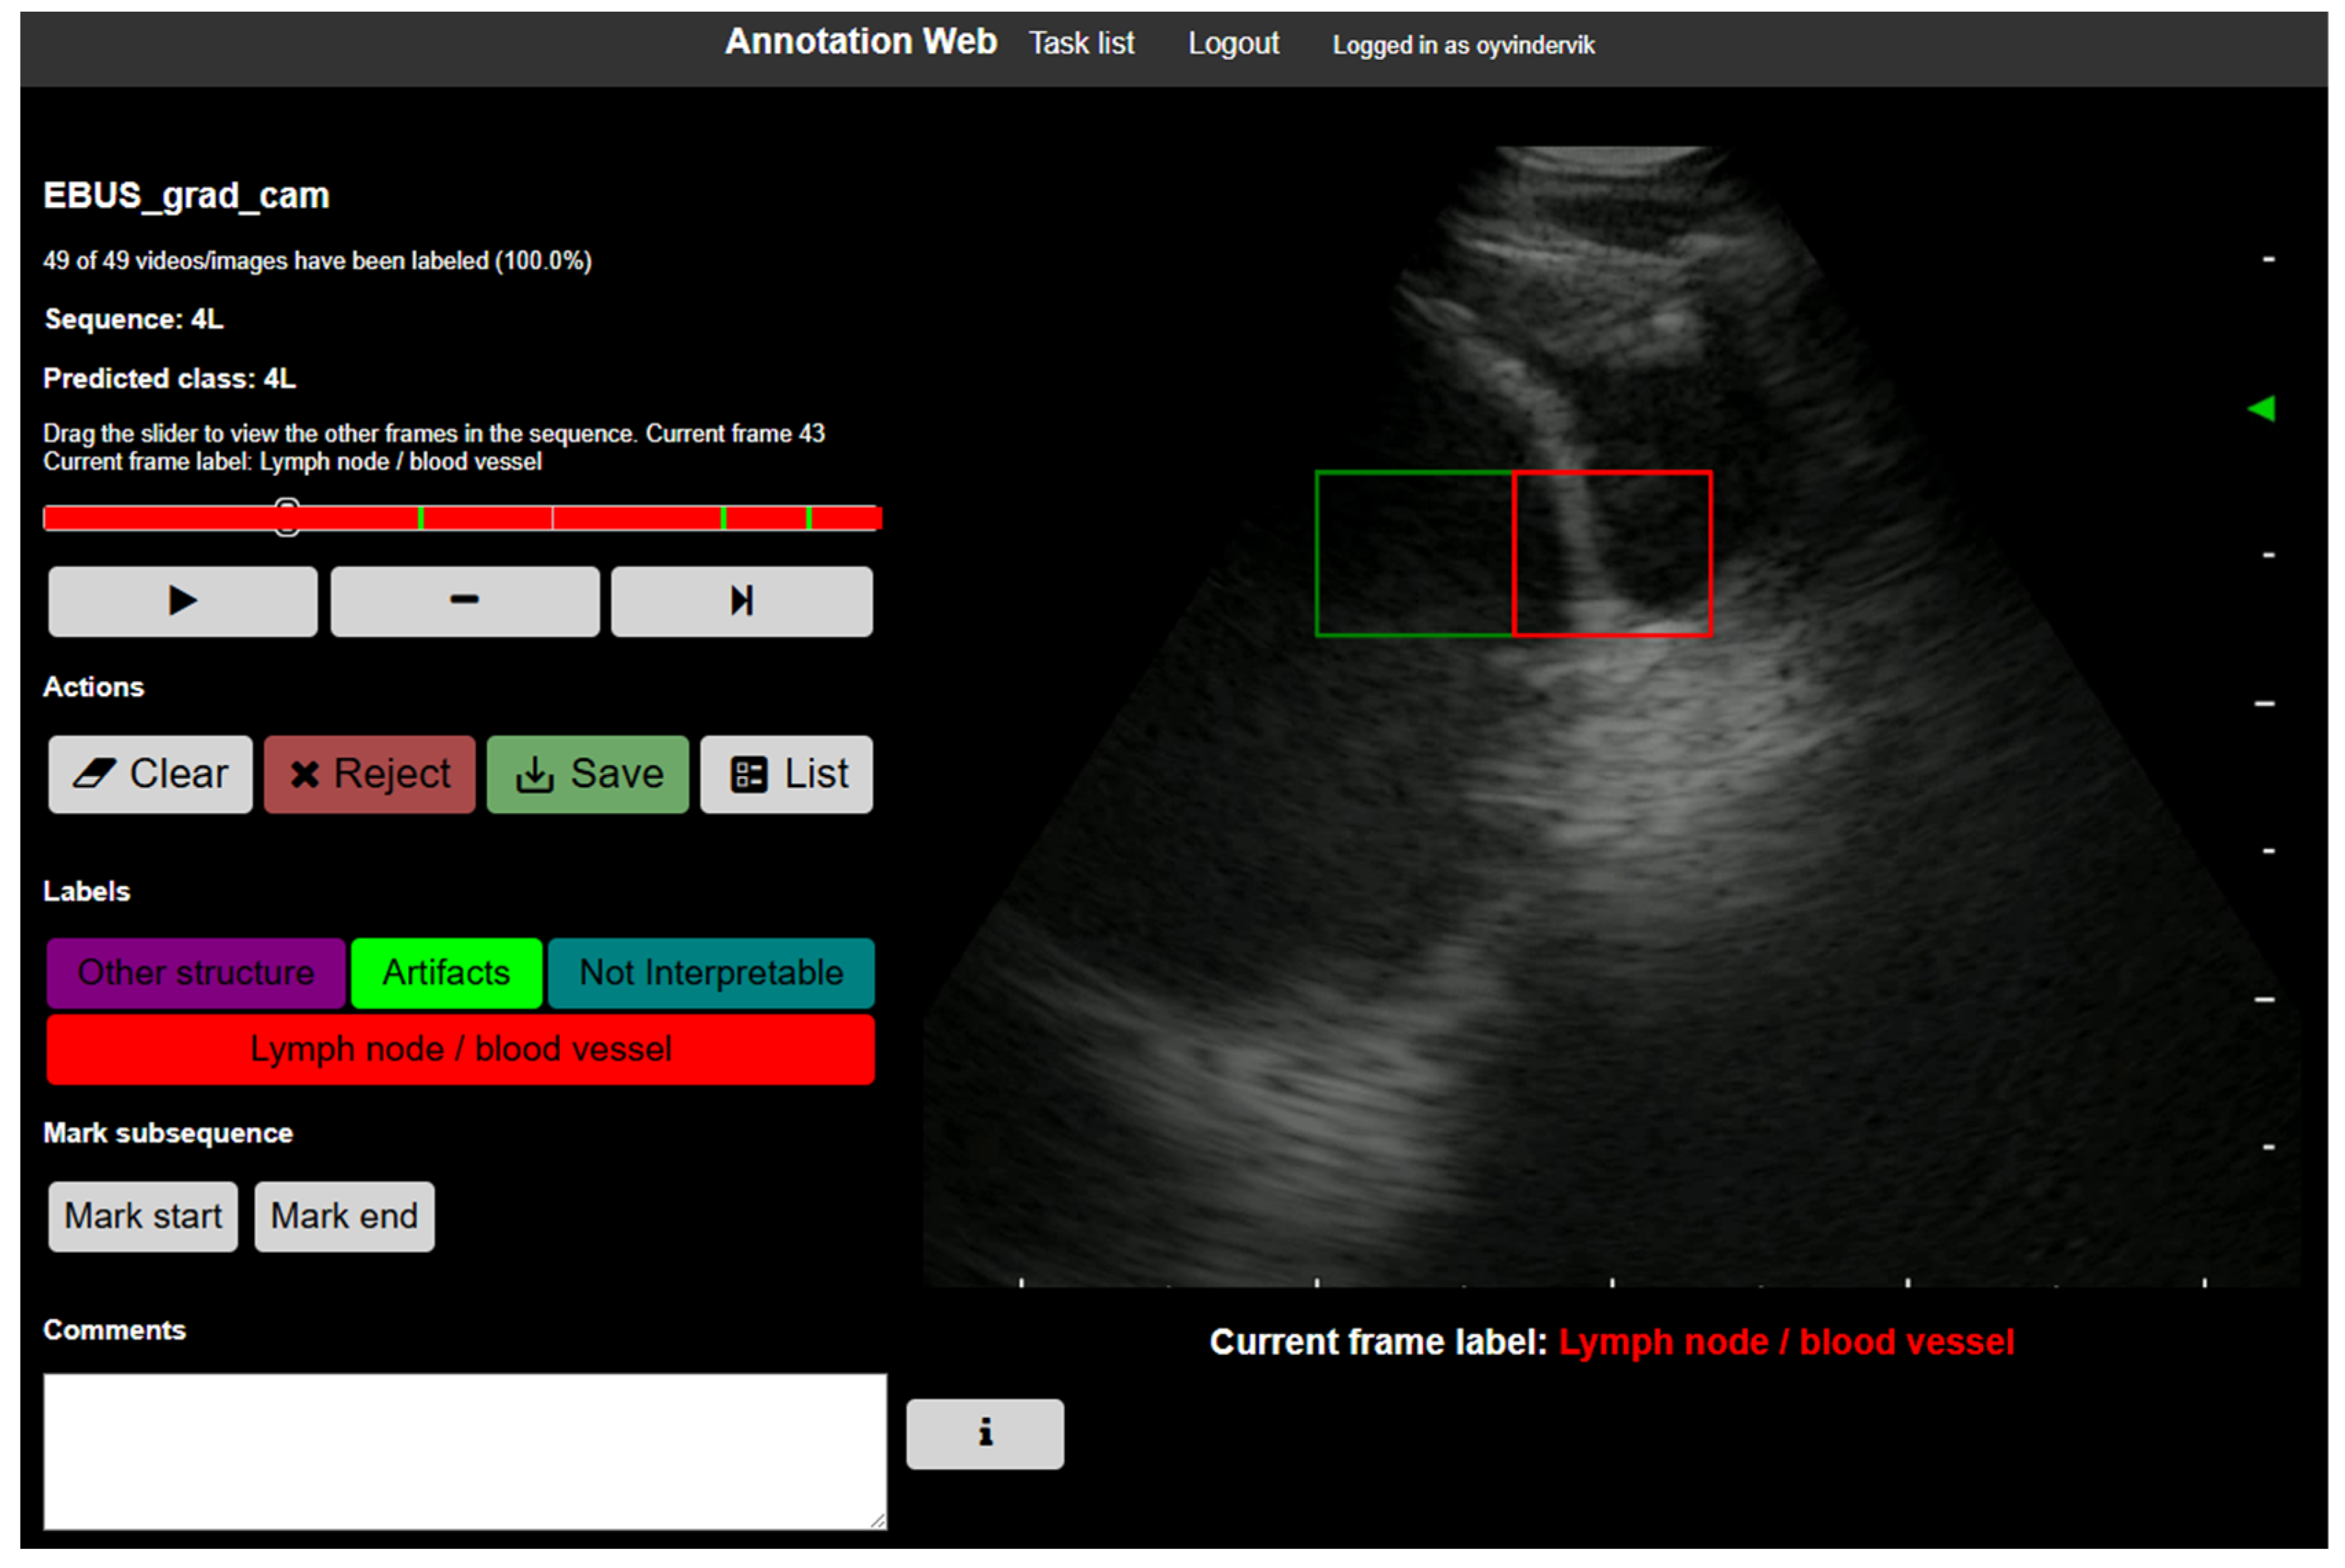

2.4.4. Expert Annotation of Grad-CAM Heatmaps

3.3.1. Annotation Workflow

- Smistad, E.; Østvik, A.; Løvstakken, L. Annotation Web—An open-source web-based annotation tool for ultrasound images. In Proceedings of the 2021 IEEE International Ultrasonics Symposium (IUS), Xi’an, China, 11–16 September 2021. [Google Scholar]